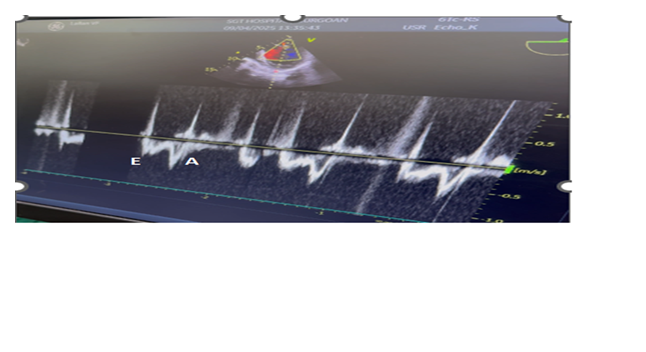

A 53 yr-male, weighing 55kg presented with occasional chest pain and palpitations and dyspnoea of NYHA class III since one year. In addition, he had progressive abdominal swelling and Intermittent dull aching pain for the last one month. Patient did not have any history of weight loss and tuberculosis. He did not consult physician for the cardiac symptoms but admitted in the surgical ward for the abdominal swelling. His biochemical and haematological values were with in normal limits. 2-D echocardiography revealed EF of 35% suggestive of severe LV systolic dysfunction, enlarged LA(4.3cm), LVEDD(5.9cms), LVESD(4.3cms), Hypokinesia of IVS and inferior wall. Mitral inflow velocity showed E<A and TDI of mitral annulus revealed a E/e’ ratio of 14 suggestive of diastolic dysfunction. ECG suggestive of AF with HR of 90 bpm and occasional PVCs. Chest X- ray was suggestive of mild to moderate cardiomegaly.

In OR, the anaesthesia technique was planned considering the patient with chronic coronary disease. Accordingly, all standard ASA monitors were attached (ECG, non-invasive BP, SPO2, EtCO2, temperature). His HR was 104bpm, BP -144/86 mmHg, arterial saturation -99% on room air, and ECG revealed AF and occasional PVCs. In view of the severe ventricular dysfunctions, infusions of levosimendan (0.1mcg/kg/min), dobutamine(2.5mcg/kg/min) and NTG(0.5mcg/kg/min) were started for cardiac support to stabilize the hemodynamic during anaesthetic and surgical manipulations. General anaesthesia was induced and maintained with etomidate (18mg), sevoflurane (1 MAC), midazolam (2mg), fentanyl (100mcg), acetaminophen (15mg/kg), and vecuronium (8mg) was used to facilitate the endotracheal intubation with 8.5 mm, ID cuffed tube. Transesophageal echocardiography (TEE) probe [GE,6TC-RS, Vivid T9 V205, Norway] was inserted after tracheal intubation. It also revealed severe LV systolic dysfunction, diastolic dysfunction, with global hypokinesia, mild MR with first order chordae rupture that is free floating in LA and LVEF of 20-25%. (Figure 2 & Video 1,2). A 20G, arterial catheter was placed in the right radial artery to measure beat to beat blood pressure and serial arterial blood gas analysis. A 7.5 F Swan Ganz, thermodilution, PA catheter was inserted via the right internal jugular vein. After the catheter was withdrawn and reinserted, it reached the RV at the second insertion. However, multiple premature ventricular contractions (PVCs) occurred while it was migrating from RV to PA, thus resulting in hypotension, which converted to VF during final manipulation for the PCWP position.